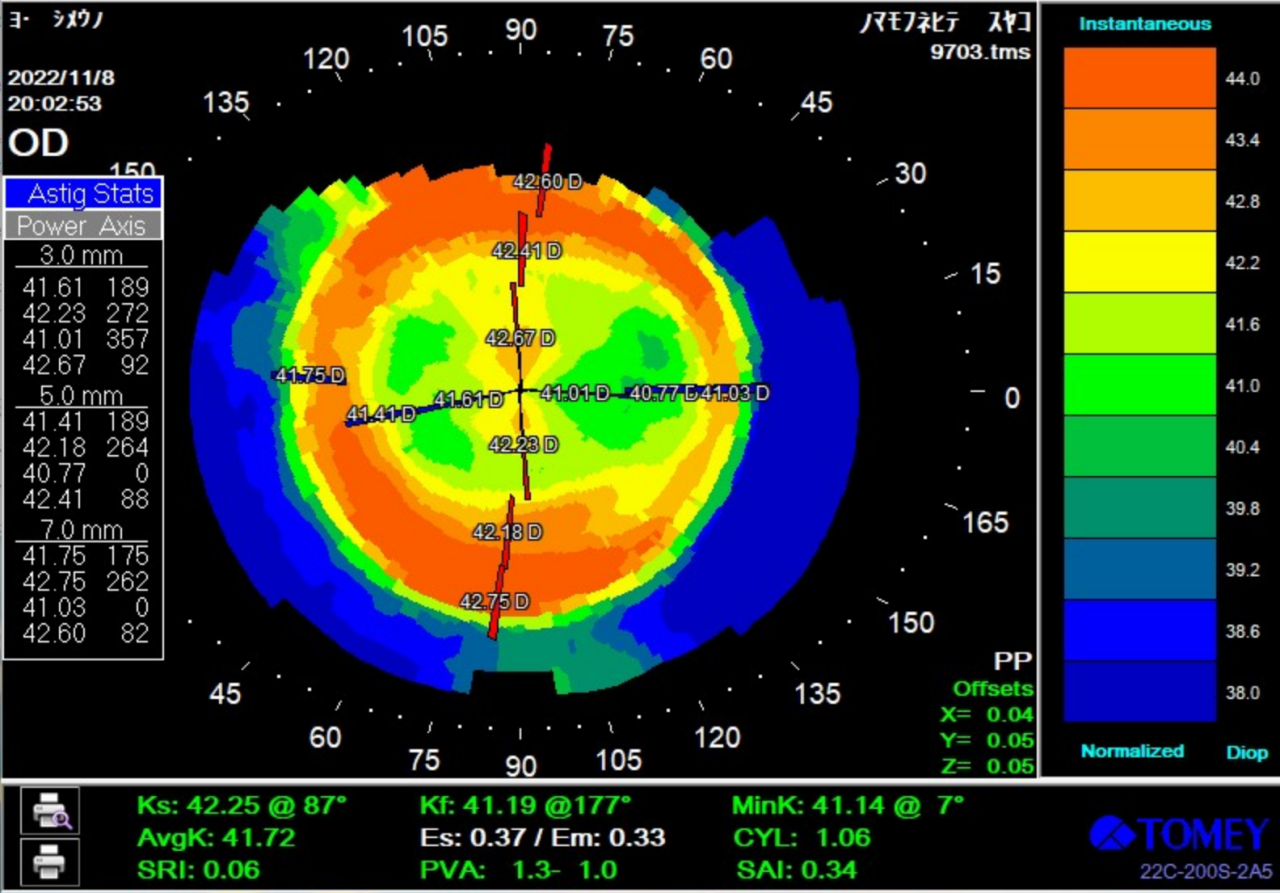

童享试戴后地形图

OD

OD:活动度良好,镜片直径适中,镜片定位居中,BC区略小,RC稍宽